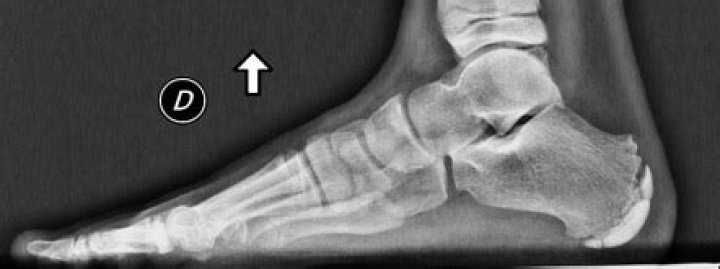

Are x-rays important? Yes, they can help rule out fractures, infections and tumors. There is no pathognomonic finding for Sever's disease.

DIAGNOSIS. If the pain persists for several weeks, a consultation with an orthopedic specialist is recommended for appropriate diagnosis. Physicians cannot detect Sever's disease by x-ray, but often an x-ray is taken to rule out other causes of pain.